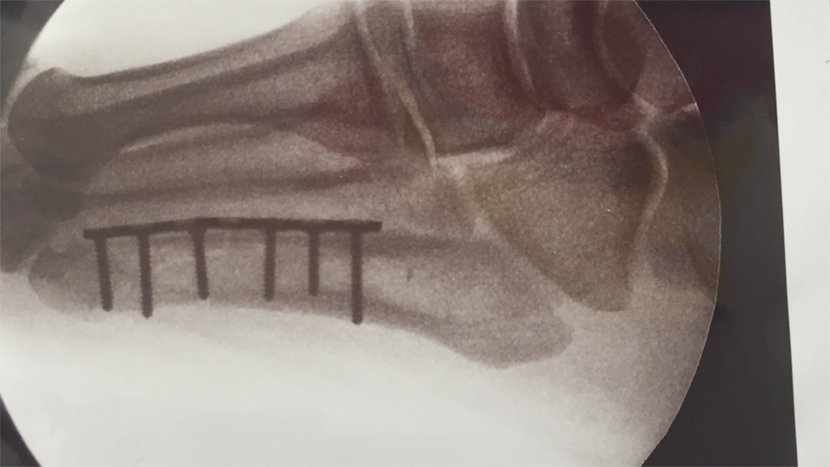

Earlier today (April 08th) Guns N’ Roses frontman Axl Rose confirmed he recently broke his foot. Despite the injury, he plans to play the band’s various upcoming ‘reunion’ shows. A surgical procedure has already been performed with a plate and numerous steel screws inserted into his foot. An video detailing his injury via his orthopedic surgeon has been shared below through Vimeo, which seemingly crashed the entire Vimeo site shortly after.

Axl Rose's Foot